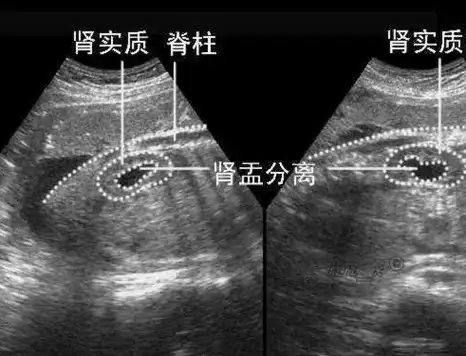

快拿出b超上的照片,教你怎么自己看孩子性别,大夫也是这样判断_胎儿